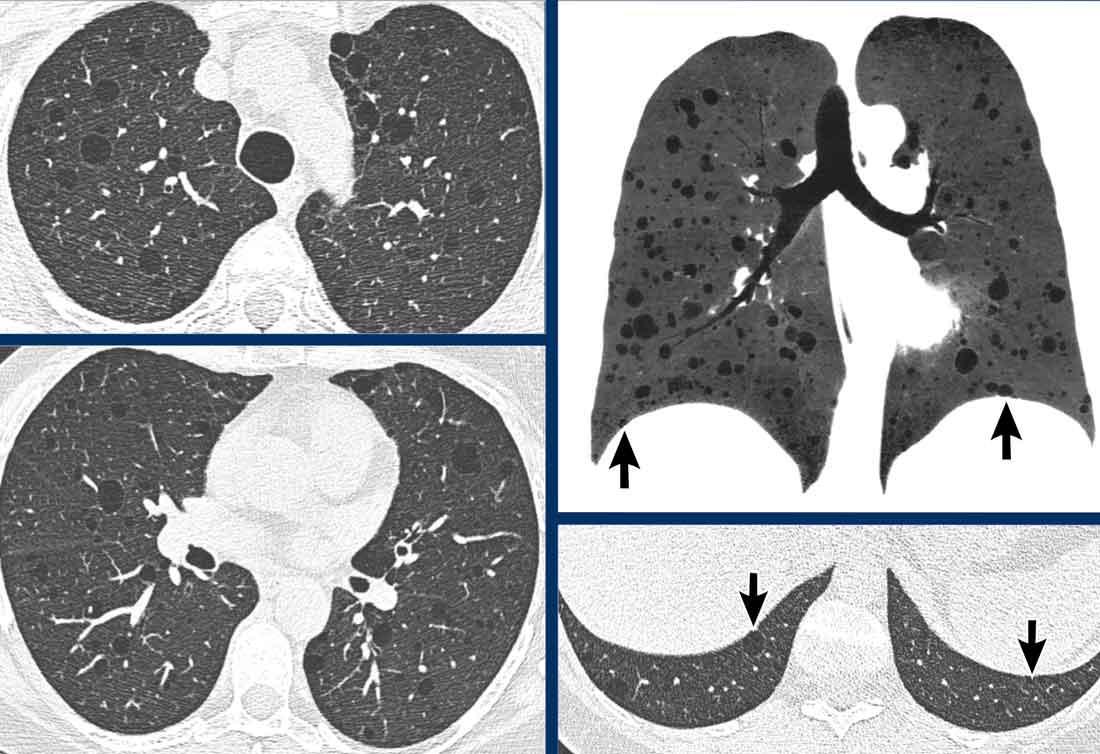

LAM biểu hiện với số lượng lớn các nang hình tròn, bờ đều đặn, phân bố rải rác khắp nhu mô phổi.

- Nhiều nang ở một phụ nữ trẻ. Lưu ý hình dạng tròn đều và phân bố lan tỏa.

- Trường hợp LAM nặng. Khi có tiền sử hút thuốc lá, chẩn đoán phân biệt cần đặt ra là LCH (giai đoạn tiến triển).

- Tràn dịch màng phổi (dịch dưỡng chấp) ở bệnh nhân LAM.

- Phân bố lan tỏa trong LAM.

Các hình ảnh này thuộc về một phụ nữ 39 tuổi với triệu chứng khó thở.

Chẩn đoán có khả năng nhất là gì?

Nhận xét hình ảnh

Có nhiều nang thành mỏng.

Lưu ý các nang phân bố đều khắp hai phổi.

Các ngách màng phổi cũng bị tổn thương (mũi tên).

Điều này cho phép loại trừ chẩn đoán LCH.

Chẩn đoán có khả năng nhất là LAM.

Đây là một ví dụ khác của LAM.

Có nhiều nang thành mỏng phân bố đều khắp hai phổi, điển hình cho LAM, nhưng trong trường hợp này kết hợp với tràn dịch màng phổi bên phải (mũi tên).

Các tế bào LAM có thể gây tắc nghẽn hệ thống bạch huyết trong lồng ngực và tạo ra tràn dịch màng phổi dưỡng chấp.

LAM là bệnh phổi dạng nang duy nhất có thể thấy sự kết hợp giữa các nang và tràn dịch màng phổi.

Ngoài ra, nhiều u cơ mỡ mạch máu (angiomyolipoma) được phát hiện ở vùng bụng trên.

Bệnh nhân này được xác định mắc LAM liên quan đến phức hợp xơ cứng củ (TSC – tuberous sclerosis complex).